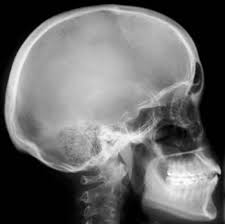

Son una radiación electromagnética de la misma naturaleza que las ondas del radio invisible, capaz de atravesar cuerpos y de fotografiar los huesos.

Los rayos X son una radiación ionizante porque al interaccionar con la materia produce la ionización de los átomos de la misma, es decir, origina partículas con carga (iones).